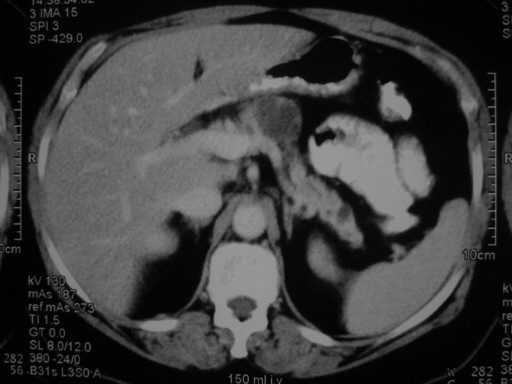

Investigation with abdominal ultrasound, CT scan and MRI with magnetic resonance cholangiopancreatography revealed two solid lesions on the right kidney, a 3.8 cm mass on the superior pole and a 1.2 cm mass on the inferior pole, both with the imaging characteristics of a renal cell carcinoma. Another 5 cm solid mass was found in the head of the pancreas, extensively compressing the antrum of the stomach and the duodenum as well as the inferior vena cava (Figure 1). The main pancreatic duct was significantly dilated and multiple cystic lesions of various sizes were also noted in the pancreatic body and tail (Figure 2). Upper GI endoscopy and endoscopic ultrasound revealed significant compression and a mucosal projection, without infiltration, on the posterior wall of the stomach and the second part of the duodenum, close to the ampulla of Vater which was caused by the pancreatic lesions. Endoscopic ultrasound-guided FNA biopsy of the lesion on the pancreatic head showed severe chronic pancreatitis. Pancreatic neuroendocrine hormones and urinary metanephrine excretion were within normal range. With a clinical diagnosis of von Hippel-Lindau disease, the patient underwent genetic evaluation which was positive for mutation R161P in exon 3 of the von Hippel-Lindau gene, in heterozygosis (direct sequencing).

Figure 2. Contrast-enhanced CT depicting two cystic lesions at the body and tail of the pancreas. |